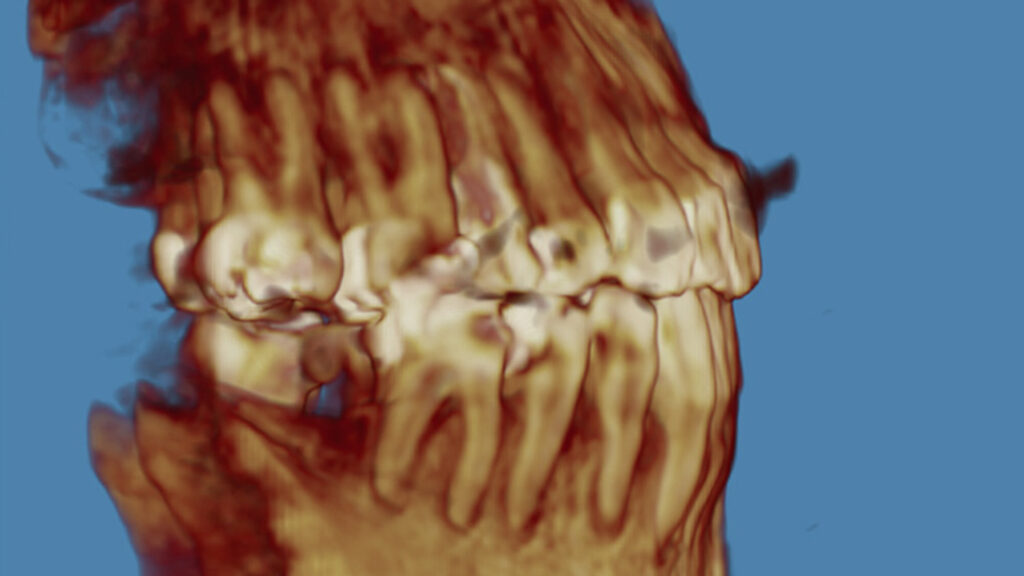

Intraoral examination showed an Angle Class III relationship on both sides, along with an anterior open bite. Additionally, a narrow maxilla with a bilateral posterior crossbite was observed.

The primary goal of the treatment was to correct the transverse deficiency of the maxillary arch (>5 mm) and resolve the skeletal crossbite. MARPE was used to address this transverse issue.